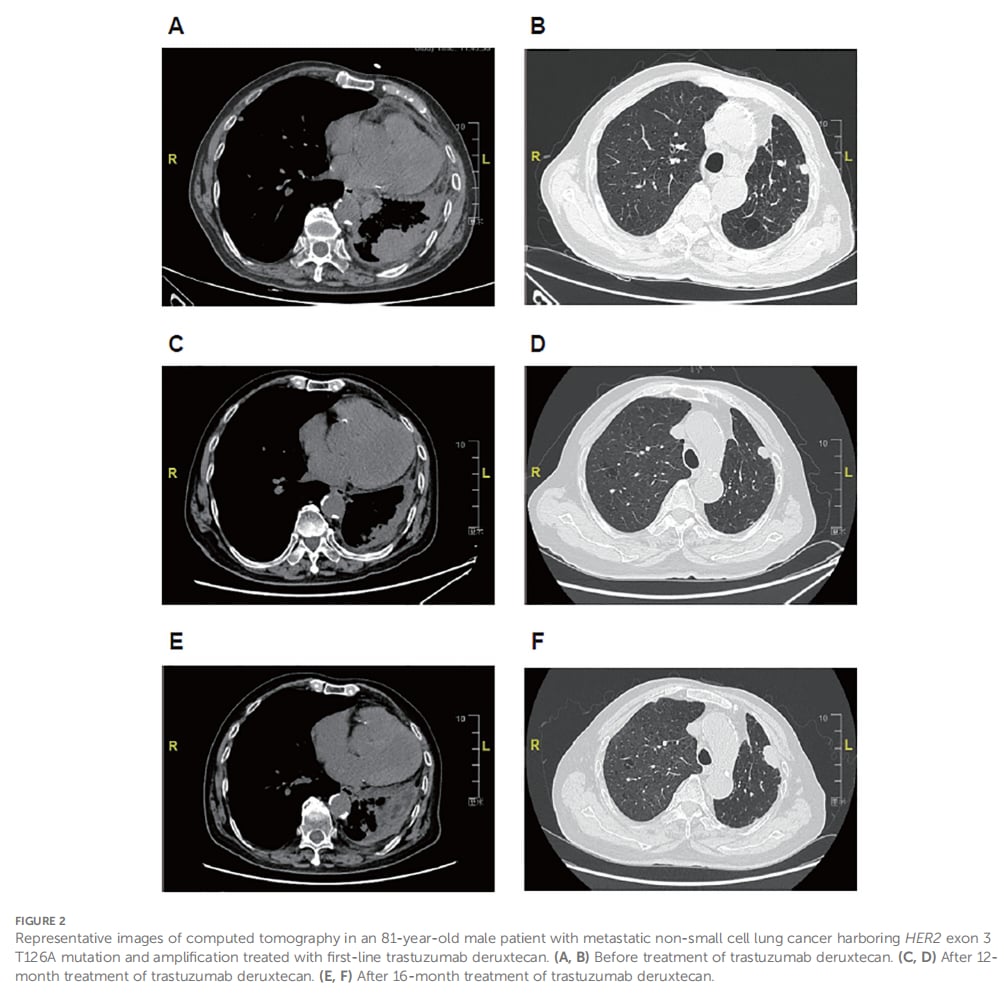

病例一:57岁女性,后线治疗显奇效

这位患者携带罕见的HER2 17外显子V659E突变,在经历多种化疗和免疫治疗方案失败后,开始接受德曲妥珠单抗作为后线治疗。令人振奋的是,治疗后她获得了部分缓解,无进展生存期(PFS)已超过13个月,且治疗仍在继续。期间出现的不良反应均为1-2级,经对症处理后得到有效控制。

▲ 图1 患者代表性CT影像